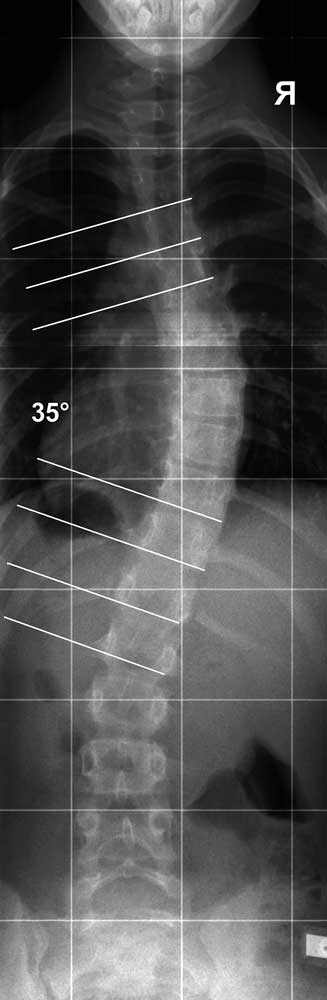

Hinter einem Cobb-Winkel der BWS von 35° kann sich z. B. die reine Seitneigung der Wirbelkörper ohne wesentliche Torsion verbergen, die sich über einen entsprechenden Wirbelsäulenabschnitt auf 35° summiert. Genauso gut kann sich hinter diesem Winkel eine 50°-Krümmung mit einem zusätzlichen Rotationsindex von 40° verbergen. Beide Szenarien erzeugen in etwa den identischen Cobb-Winkel von 35° und werden allzu oft therapeutisch gleich behandelt (in diesem Fall werden sie einer Ganztagskorsett-Therapie zugeordnet).

Die beiden Szenarien erzeugen aber höchst unterschiedliche tatsächliche Deformitäten, Thoraxquerschnitte und Lungenvolumina. Eine 50°-Krümmung, die aufgrund einer beträchtlichen Torsion im Röntgen nur 35° Cobb anzeigt, kann längst eine OP-Indikation verkörpern, wird aber als solche oft nicht wahrgenommen, da die Rotation/Torsion der BWS den Cobb-Winkel künstlich reduziert (Abb. 2).